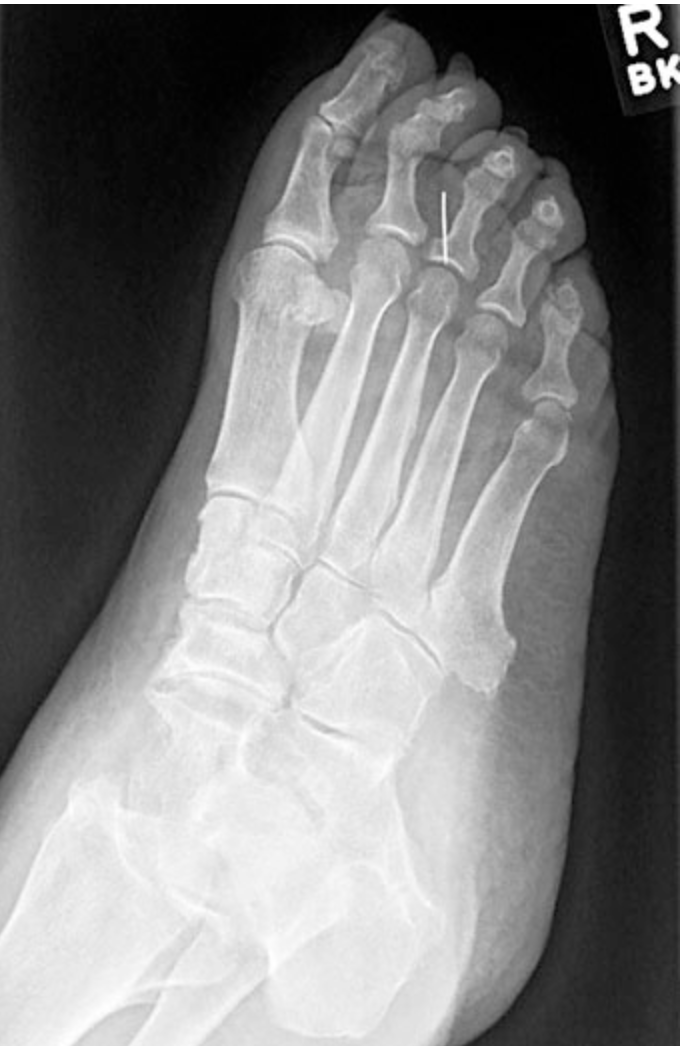

A 52-year-old woman comes to the physician because of a 1-week history of swelling of the ball of her right foot. She remembers that she saw a small area of blood on the floor after she rose to take a break from sewing. She was not wearing shoes at the time. When she looked, she did not see anything on her feet. She has type 2 diabetes mellitus, retinopathy, and hypertension. She does not measure her blood glucose concentration regularly; her last hemoglobin A1c4 weeks ago was 10%. Her medications are metformin, glyburide, and hydrochlorothiazide. She is 157 cm (5 ft 2 in) tall and weighs 109 kg (240 lb); BMI is 44 kg/m2. Her temperature is 37.8°C (100°F), and blood pressure is 145/85 mm Hg. Examination shows a 2-mm, superficial wound over the plantar aspect of the right foot between the second and third metatarsophalangeal joints. There is edema and tenderness to palpation over the right forefoot, particularly over the third metatarsophalangeal joint. Dorsalis pedis pulses are not palpable bilaterally. Semmes-Weinstein 5.07 monofilament testing shows decreased sensation over both feet. An x-ray of the right foot is shown. Which of the following is most likely to have prevented this patient’s current condition?